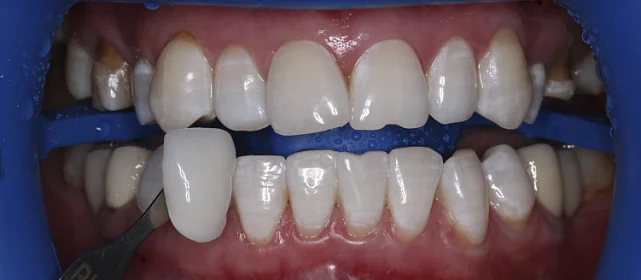

Результат

Зубы выровнены, смыкание нормализовано. Установлены несъёмные ретейнеры на обе челюсти. Пациент направлен к ортопеду.

Решение: Поставили элайнеры Invisalign на обе челюсти. Лечение заняло 4 года — случай потребовал нескольких этапов коррекции, каждый из которых последовательно приближал зубы к нужному положению. Капы менялись каждые 1–2 недели, контрольные визиты — для отслеживания прогресса и выдачи новых наборов. Зубы встали на место, смыкание пришло в норму. Зафиксировали ретейнеры на обе челюсти, пациент направлен к ортопеду для завершающего этапа.